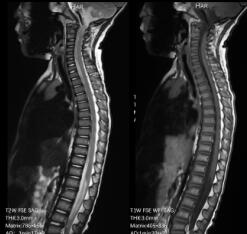

全脊柱成像

具备较高图像分辨率可清晰显示颈、胸、腰骶椎,对脊髓炎、椎体弥漫性病变等疾病的诊断有较大价值。